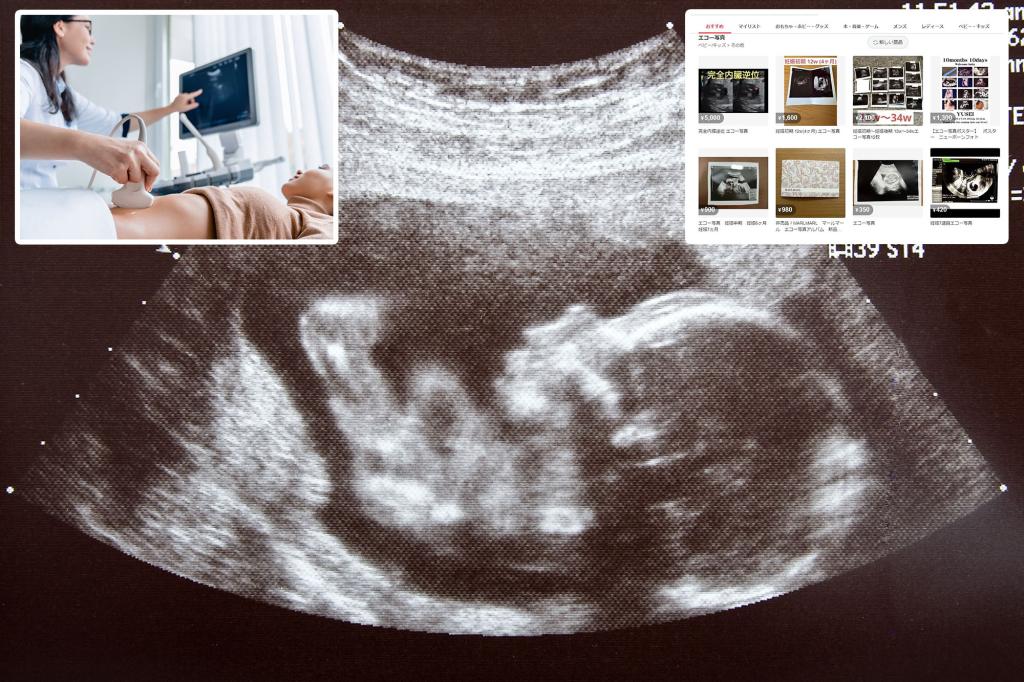

الآن ، قامت Mercari بسحب القابس على بيع لقطات الموجات فوق الصوتية (التي تم بيعها مرة واحدة عبر الإنترنت بحوالي 14 دولارًا ، وفقًا لمستخدمي X) ، حيث ينحني لأولئك الذين يشعرون بالقلق بشأن كيفية التقاط الغرباء صورًا قبل الولادة.

حظر الحظر بعد عرض الفيروسي X Post قوائم Mercari المكشوفة صور الموجات فوق الصوتية والصور لاختبارات الحمل الإيجابية.

لم تشرح Mercari أكثر ، ولكن اعتبارًا من 1 سبتمبر ، يتم حظر الصور بالموجات فوق الصوتية رسميًا في السوق ، وفقًا لـ Soranews24.